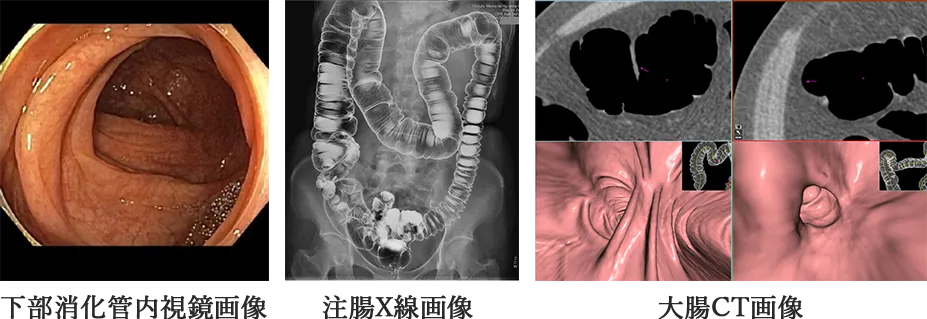

健診やドックで便潜血検査が陽性になった場合は精密検査として、下部消化管内視鏡検査(大腸内視鏡)、大腸CT検査、注腸X線検査(バリウム検査)が行われます。早期発見・早期治療により、大腸がんの完治率は非常に高くなりますので、定期的な検査をお受けになることをお勧めします。

便潜血検査、下部消化管内視鏡検査、注腸X線検査(バリウム)、大腸CT検査などがあります。

スライス厚(裁断面の厚み)1.0mm以下で収集された約1000枚の画像を専用の解析ソフトへ取り込み、三次元画像を作成します。腸管内腔を多断面から観察するMPR法(multiplanar reconstraction)、大腸全体を透かした画像(air image)、仮想内視鏡画像(virtual endoscopy)、仮想展開画像(virtual gross pathology)などにより、大腸内腔の粘膜を詳細に観察してゆきます。検出精度の向上に伴い、6.0mmより大きなポリープの検出能は下部消化管内視鏡検査と比べ同等以上とされています。